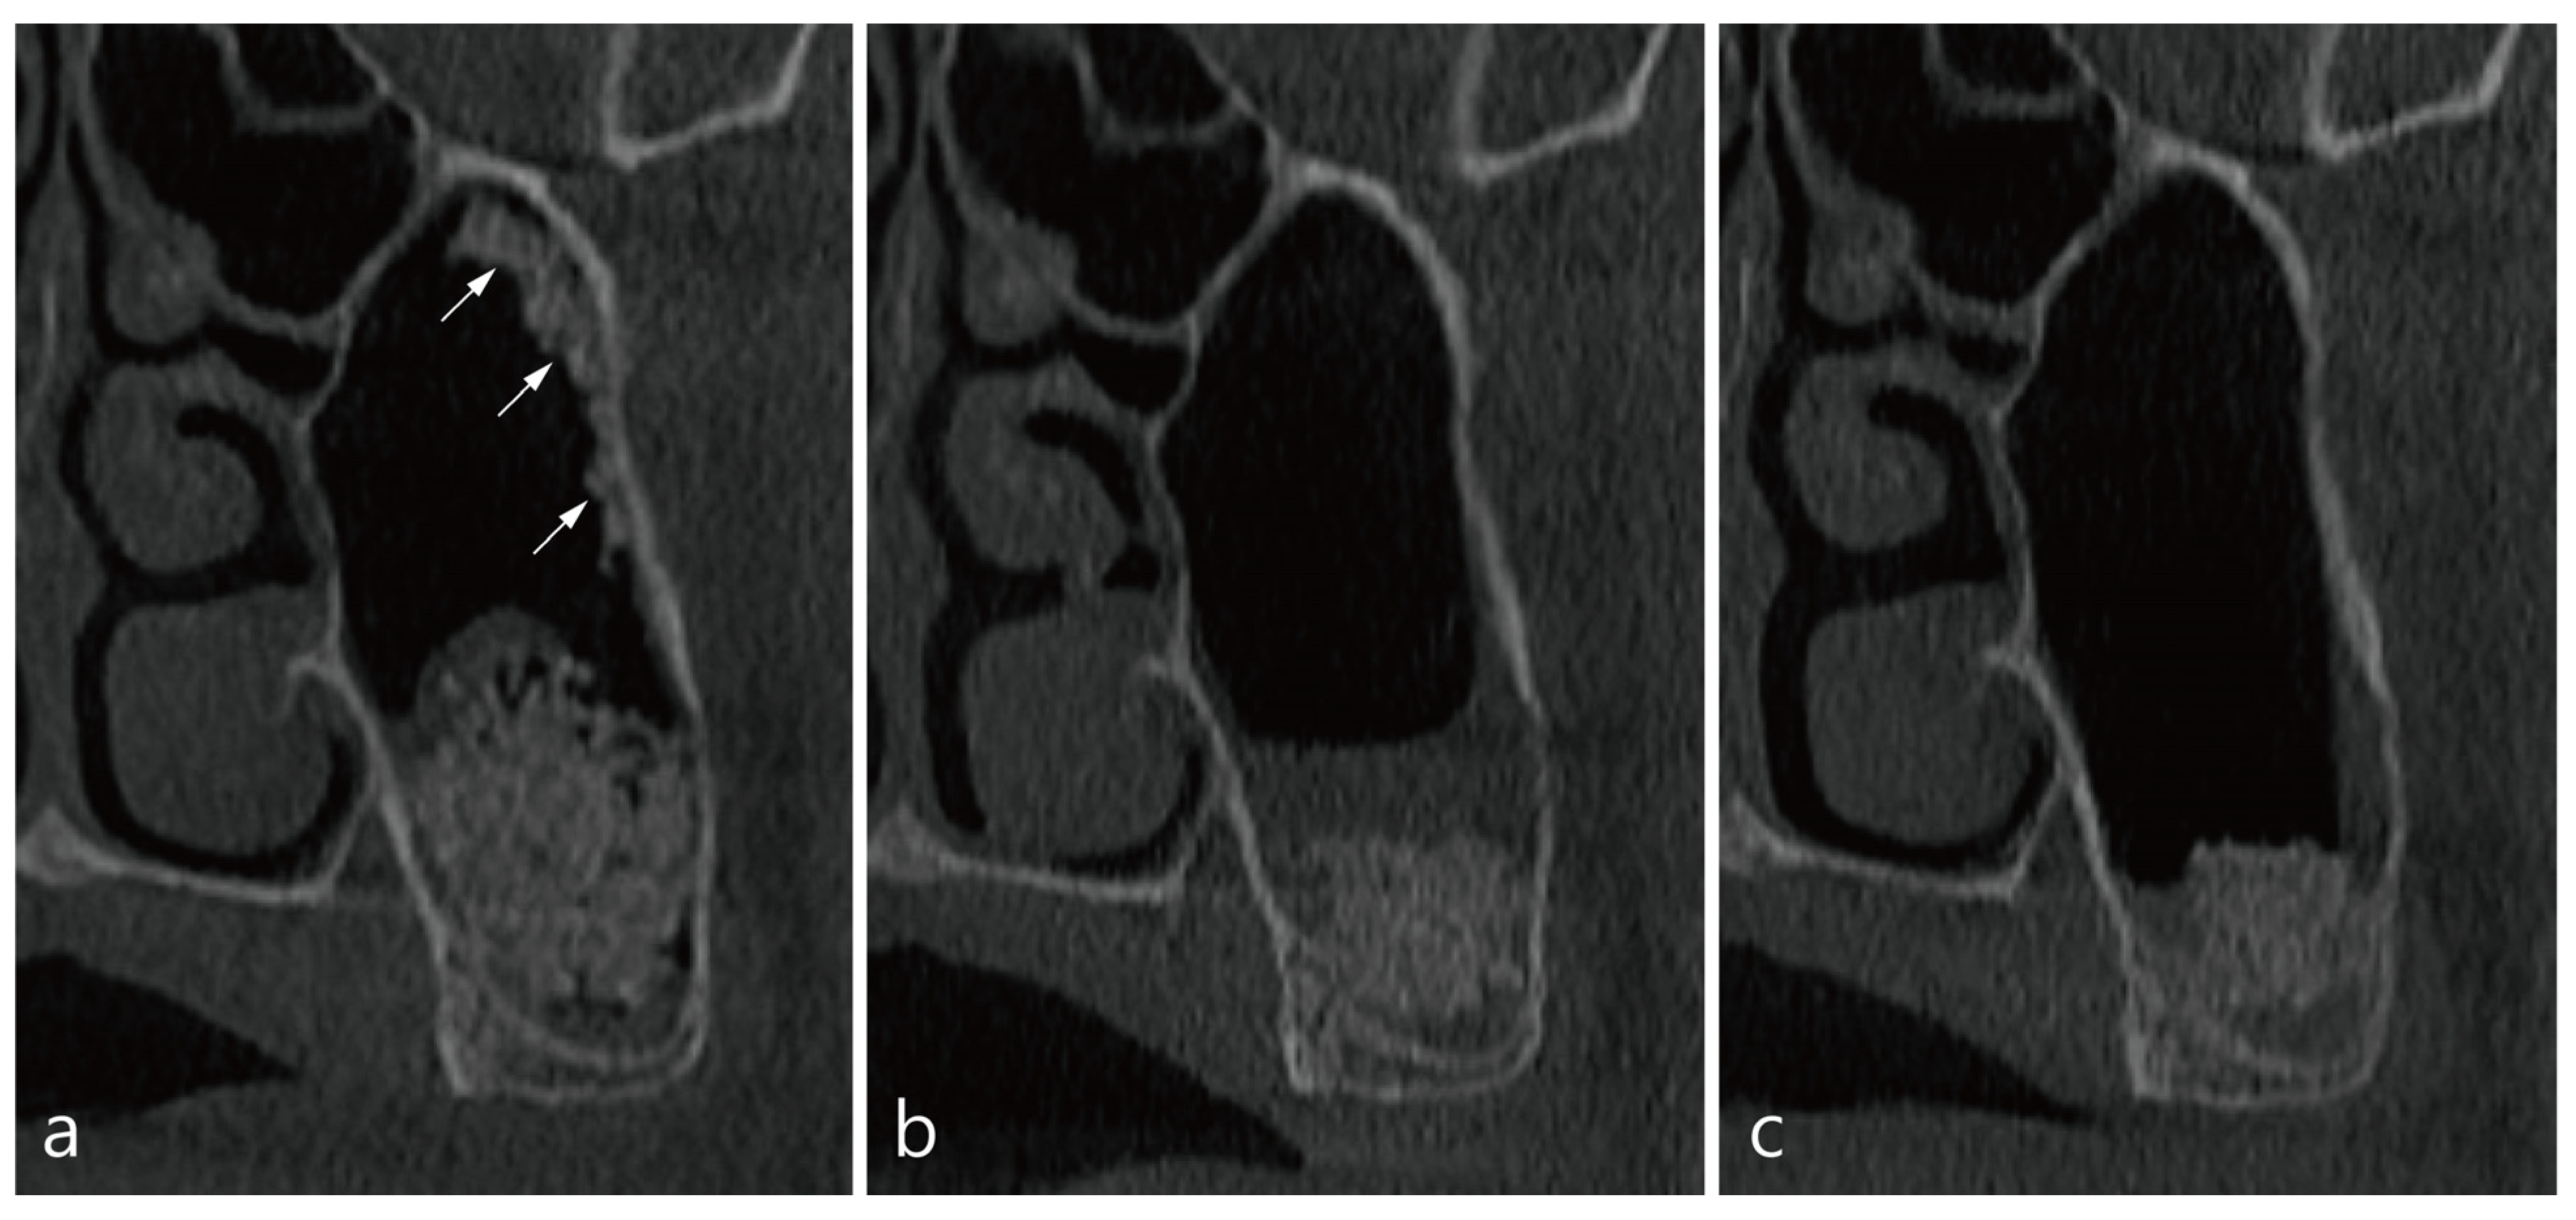

2. Presentation of Cases

3. Case 1

4. Case 2

5. Case 3

6. Case 4